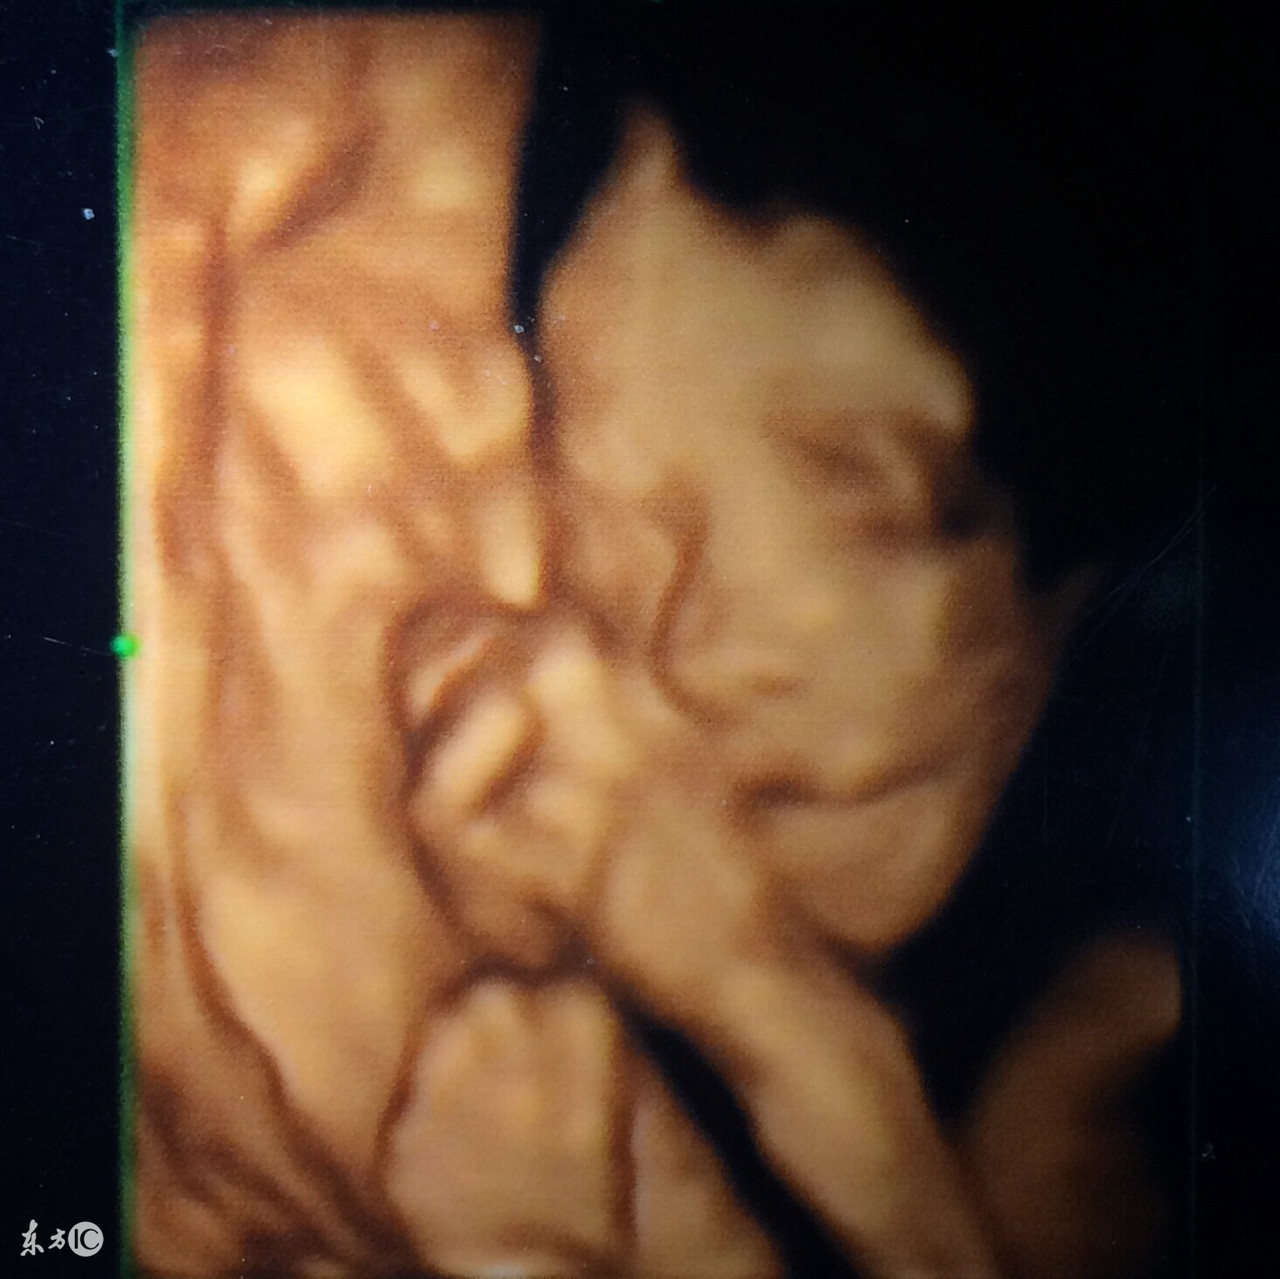

三维彩超、四维彩超的图像是后期生成的,并不是说观察到的图像就是三维、四维的,而是仍然用普通彩超观察,然后通过仪器中的转换软件将观察到的 平面图像转成三维、四维的立体图像,使不懂B超图像的人也能看出胎儿的模样。这类B超不是孕期检查必选的,如果准爸妈很想看到胎儿的样子和在子宫里的动作,这类B超会看的更清楚。